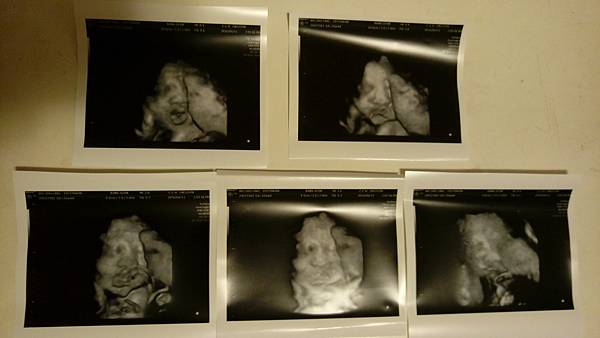

在近一點時總算叫到我了,由於是第一次給謝醫師看診,所以圓圓我一丁丁都不敢造次,乖乖地坐著等謝醫師看我帶去的資料與電腦上的病歷…直到謝醫師開口了我趁機提出了問題。謝醫師果真如外面的風評一樣,非常有耐心地回應我每一疑問,哈,由於小姐在翻找報告時我才發現王醫師並未把羊膜穿刺的報告給我,幸好謝醫師說報告正常就好了,不需要再回去申請,這讓我就無需趕著隔天早上回馬偕報到嚕~~;而因小姐在翻資料時有注意到我夾在媽媽手冊裡鄭醫師寫的那張,她問我那不就要剖腹產了?她的這個問題害我不禁緊張起來,當然得問清楚囉……我請教是否一定要嗎?謝醫師看了報告與鄭醫師寫的那張單子後回覆:不用啦,生生看,80%應該生的出來的…哈,這樣就不用先緊張了;至於我一直很在意的是否要打百日咳那一針,謝謝他很清楚地說明,原來是從美國整個複製過來的啊,反正要不就是我打那針以讓胎盤傳達抗體給寶寶、要不就是寶寶出生後做『袋鼠效應』-讓寶寶周遭的所有人全部去施打疫苗…欸,關於這部份,寶寶啊,應該也不容易捏~離開診間前醫師說由於我是第一次去看診,所以要我繳費後回來照超音波…之前文瑜說過謝醫師看超音波很強,不過我想說我的報告都正常,應該還好吧…當謝醫師開始檢查時,我想我明白了,只是…只是…那個彰基還真不是我要說的,螢幕那麼小一個還裝那麼遠,看得很辛苦+吃力耶@@知道寶寶正常成長,圓圓我也就更加放心了,而且先前照到的那個小白點,醫師也說不用擔心,太棒了!!